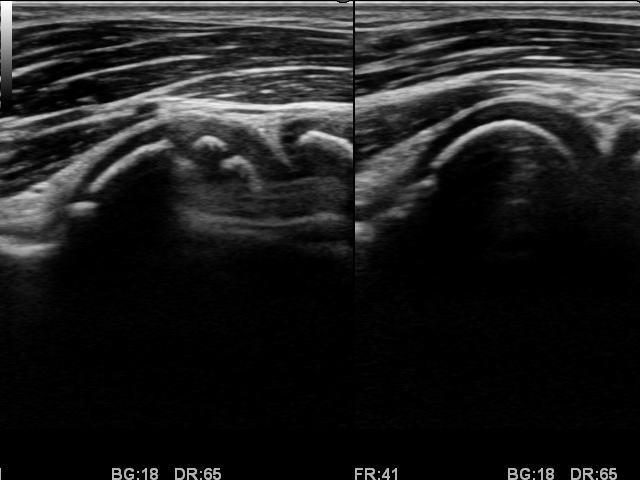

エコー検査

野球肩・野球肘のエコー

高精度エコー

最高峰の高精度エコーにより、野球肘・野球肩の細かな損傷も見逃さず、お身体の状態を把握します。

野球肩・野球肘のエコー画像

離断性骨軟骨炎

野球肘のガンとも言われる、最も難渋する疾患です。

絶対に見逃してはなりません。早期発見が最重要事項です。

エコー等の画像診断が無ければ早期発見は不可能と思われる障害です。